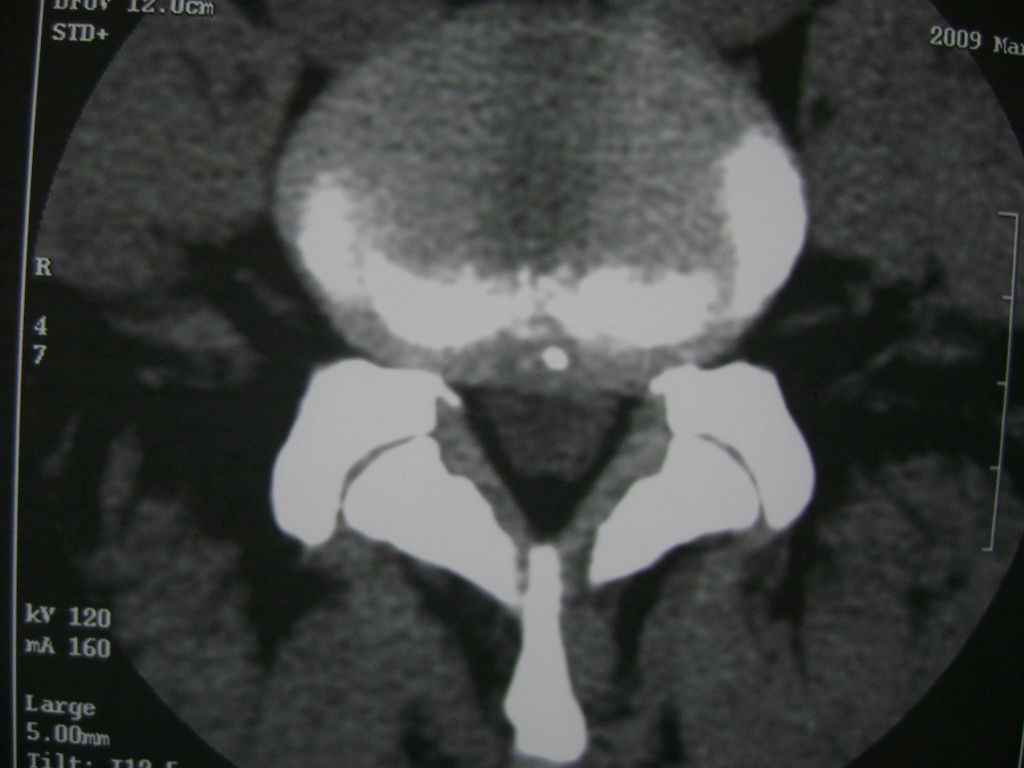

m  50  腰痛

两个椎盘均有膨出及突出改变,下一个尚有椎盘积气,后纵韧带钙化,另椎管脂肪过多症

椎间盘膨出,后纵韧带钙化,骨质增生

两个椎间盘中央型重度突出,黄韧带增厚。

两个椎间盘膨出并突出,下一个椎间盘变性;双侧黄韧带钙化。